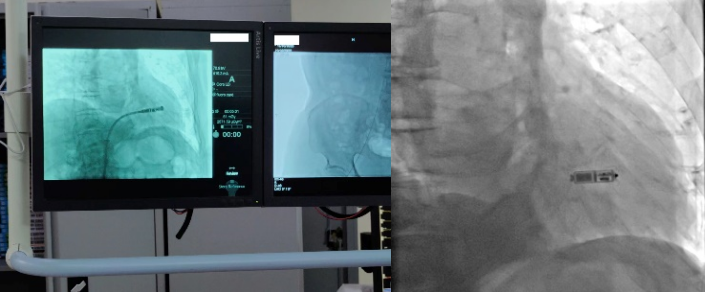

2022年11月16日,心血管内科三病区心脏介入团队在科主任孙林教授指导下,成功完成一台新一代双腔无导线起搏器植入术,通过右侧股静脉在患者心脏内“扎根”,让患者重获“心”生。

无导线起搏器是一种新兴的心脏起搏器,让“不开刀即可安装起搏器”的梦想成为现实。它身形小巧,只有胶囊大小,重仅2克。但却拥有超强的电池续航能力,寿命超过12年。同时兼容1.5T/3.0T核磁共振扫描,可满足患者之后疾病诊断需求。与传统心脏起搏器相比,双腔无导线起搏器体积减少93%,整个手术过程时间短,植入成功率高。可以保存心房、心室的顺序收缩功能,实现生理性起搏功能,开启了“无导线起搏新时代”。该技术的成功开展,是樱花动漫 心血管内科三病区不断开展新技术、持续提升服务水平的生动注脚。未来,心血管内科将持续推进该项技术的普及,为更多患者的“心健康”保驾护航。